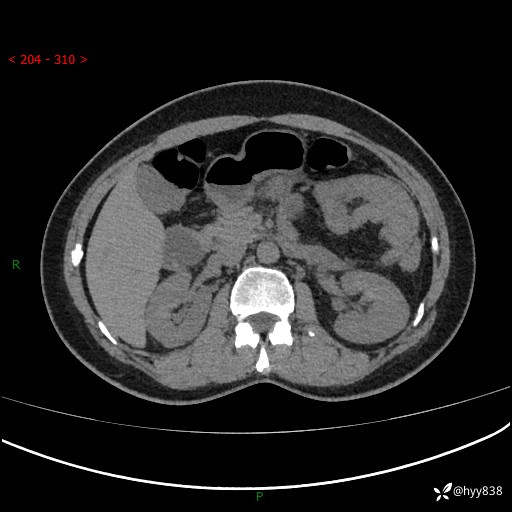

51岁/女,腹痛腹胀1天。白班偶遇,收藏教学备用---(公布详细手术过程)

现病史:患者1天前无明显诱因下出现左上腹部及腰背部胀痛不适,阵发性加剧,伴肛门停止排气;无发热,无恶心呕吐,无畏寒发热,无心慌气短等不适,于当地市第二人民医院就诊,行腹部ct检查提示左上腹区肠系膜血管从剧聚集,分布紊乱伴肠管局限性稍扩张积液,不完全性肠梗阻;考虑子宫颈纳氏囊肿,双侧附件区囊状灶;予以抗炎及对症支持等治疗后未见明显缓解,现患者为求进一步治疗来我院急诊就诊,遂以“肠梗阻”收住入院。 病来,神志清,精神可,饮食睡眠不佳,经灌肠后排便2次,小便正常,体力体重无明显变化。

上腹部CT平扫